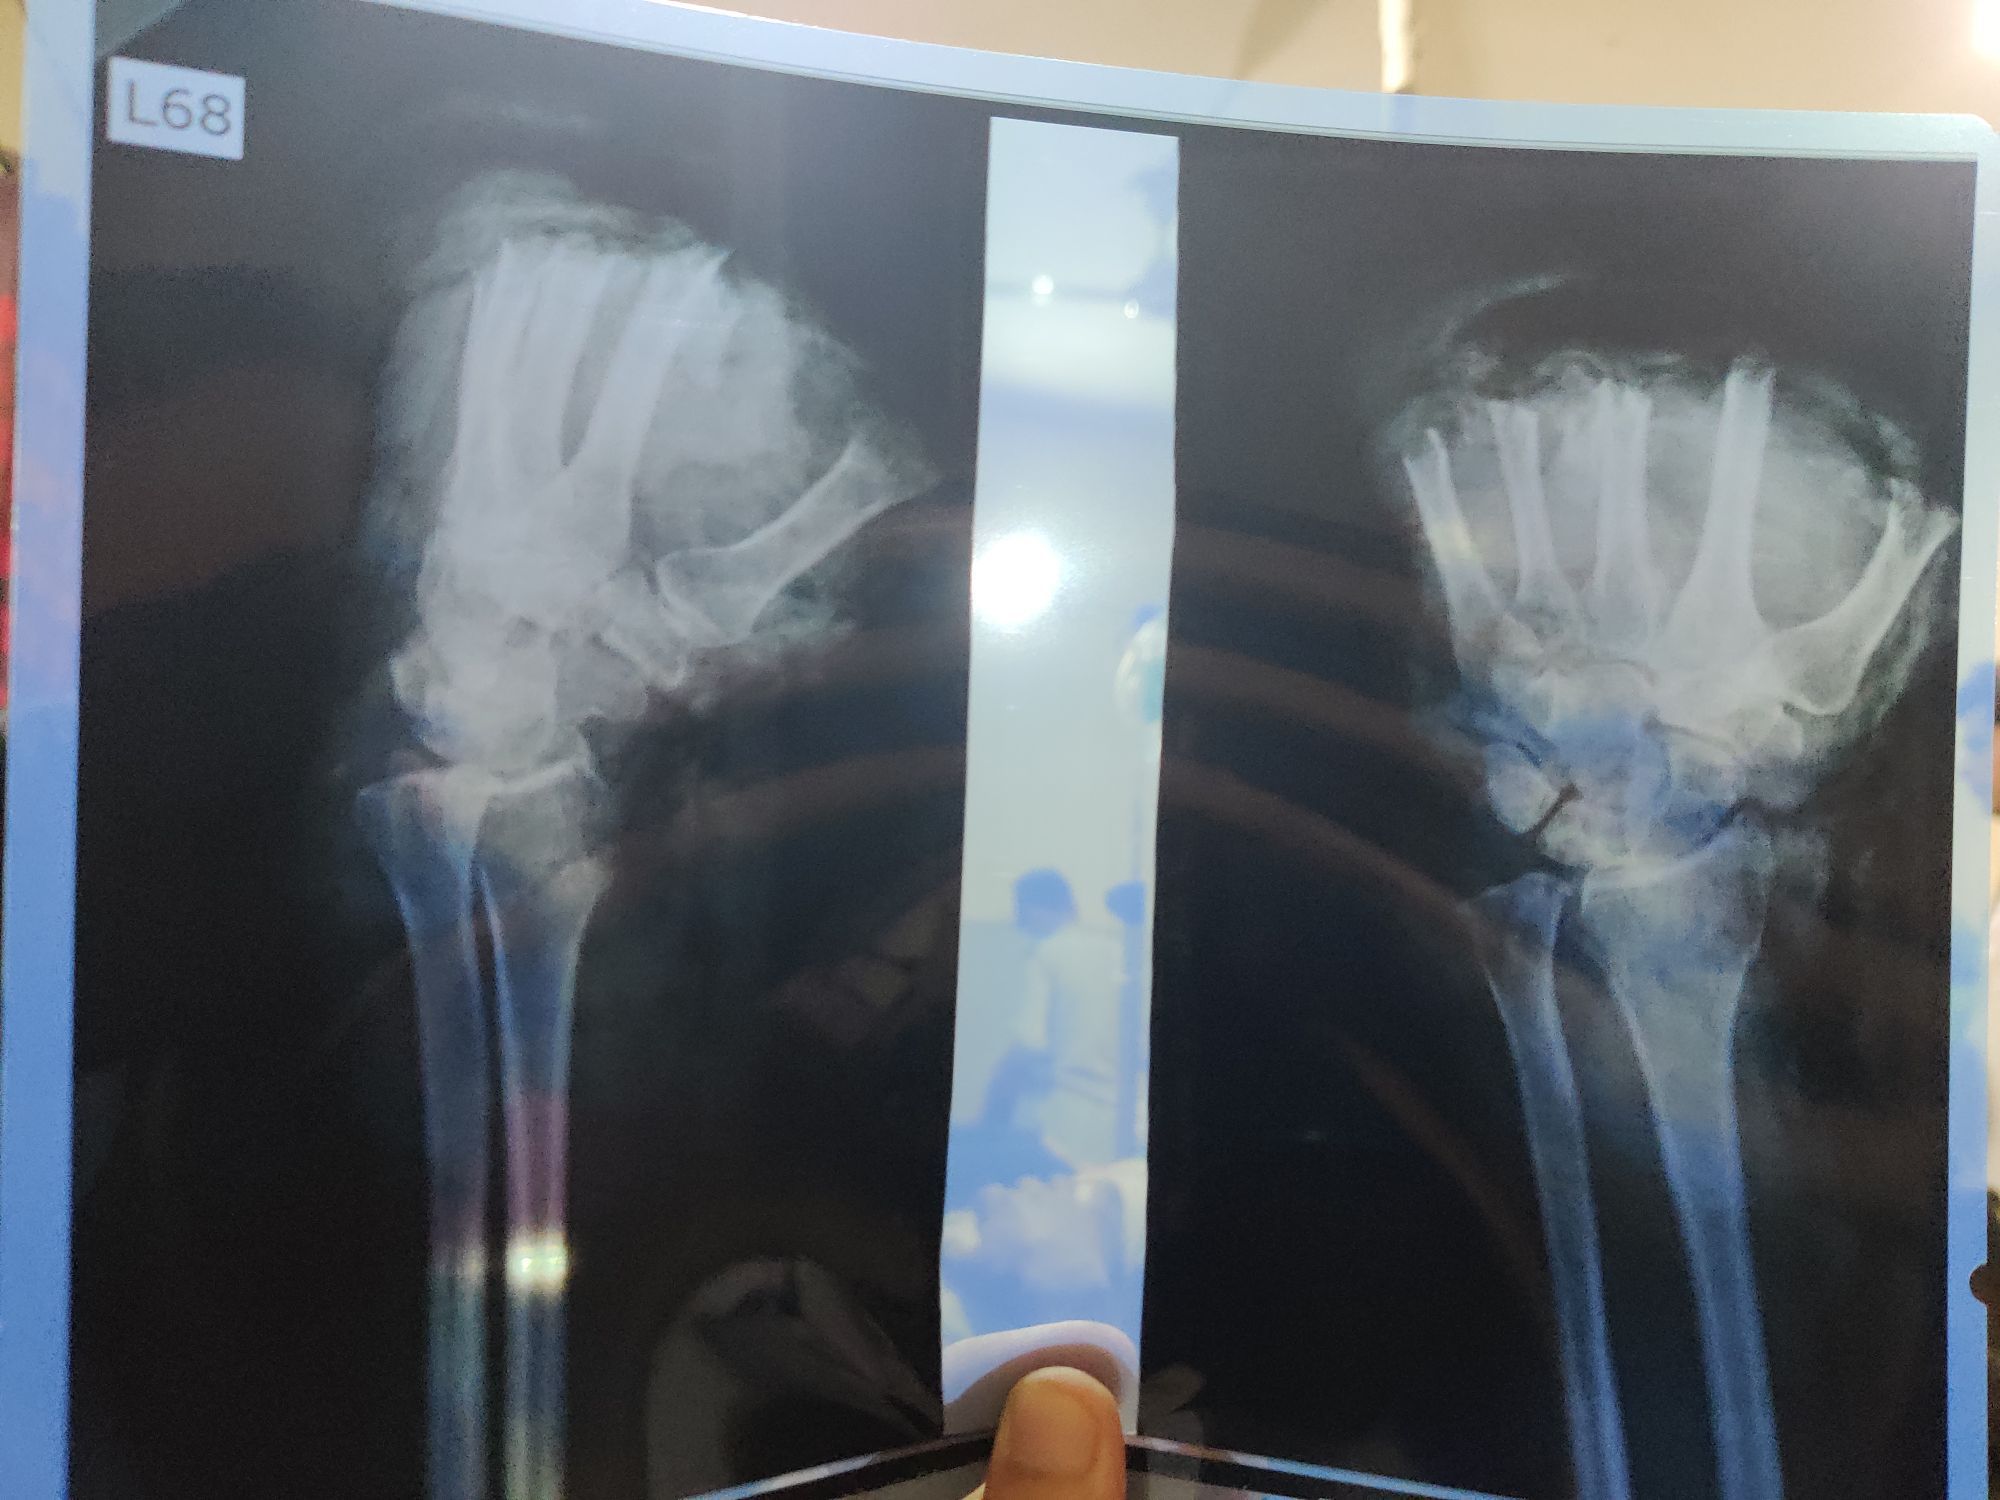

Traumatic Amputation of Phalanges

Surgery

Ortho

Rta